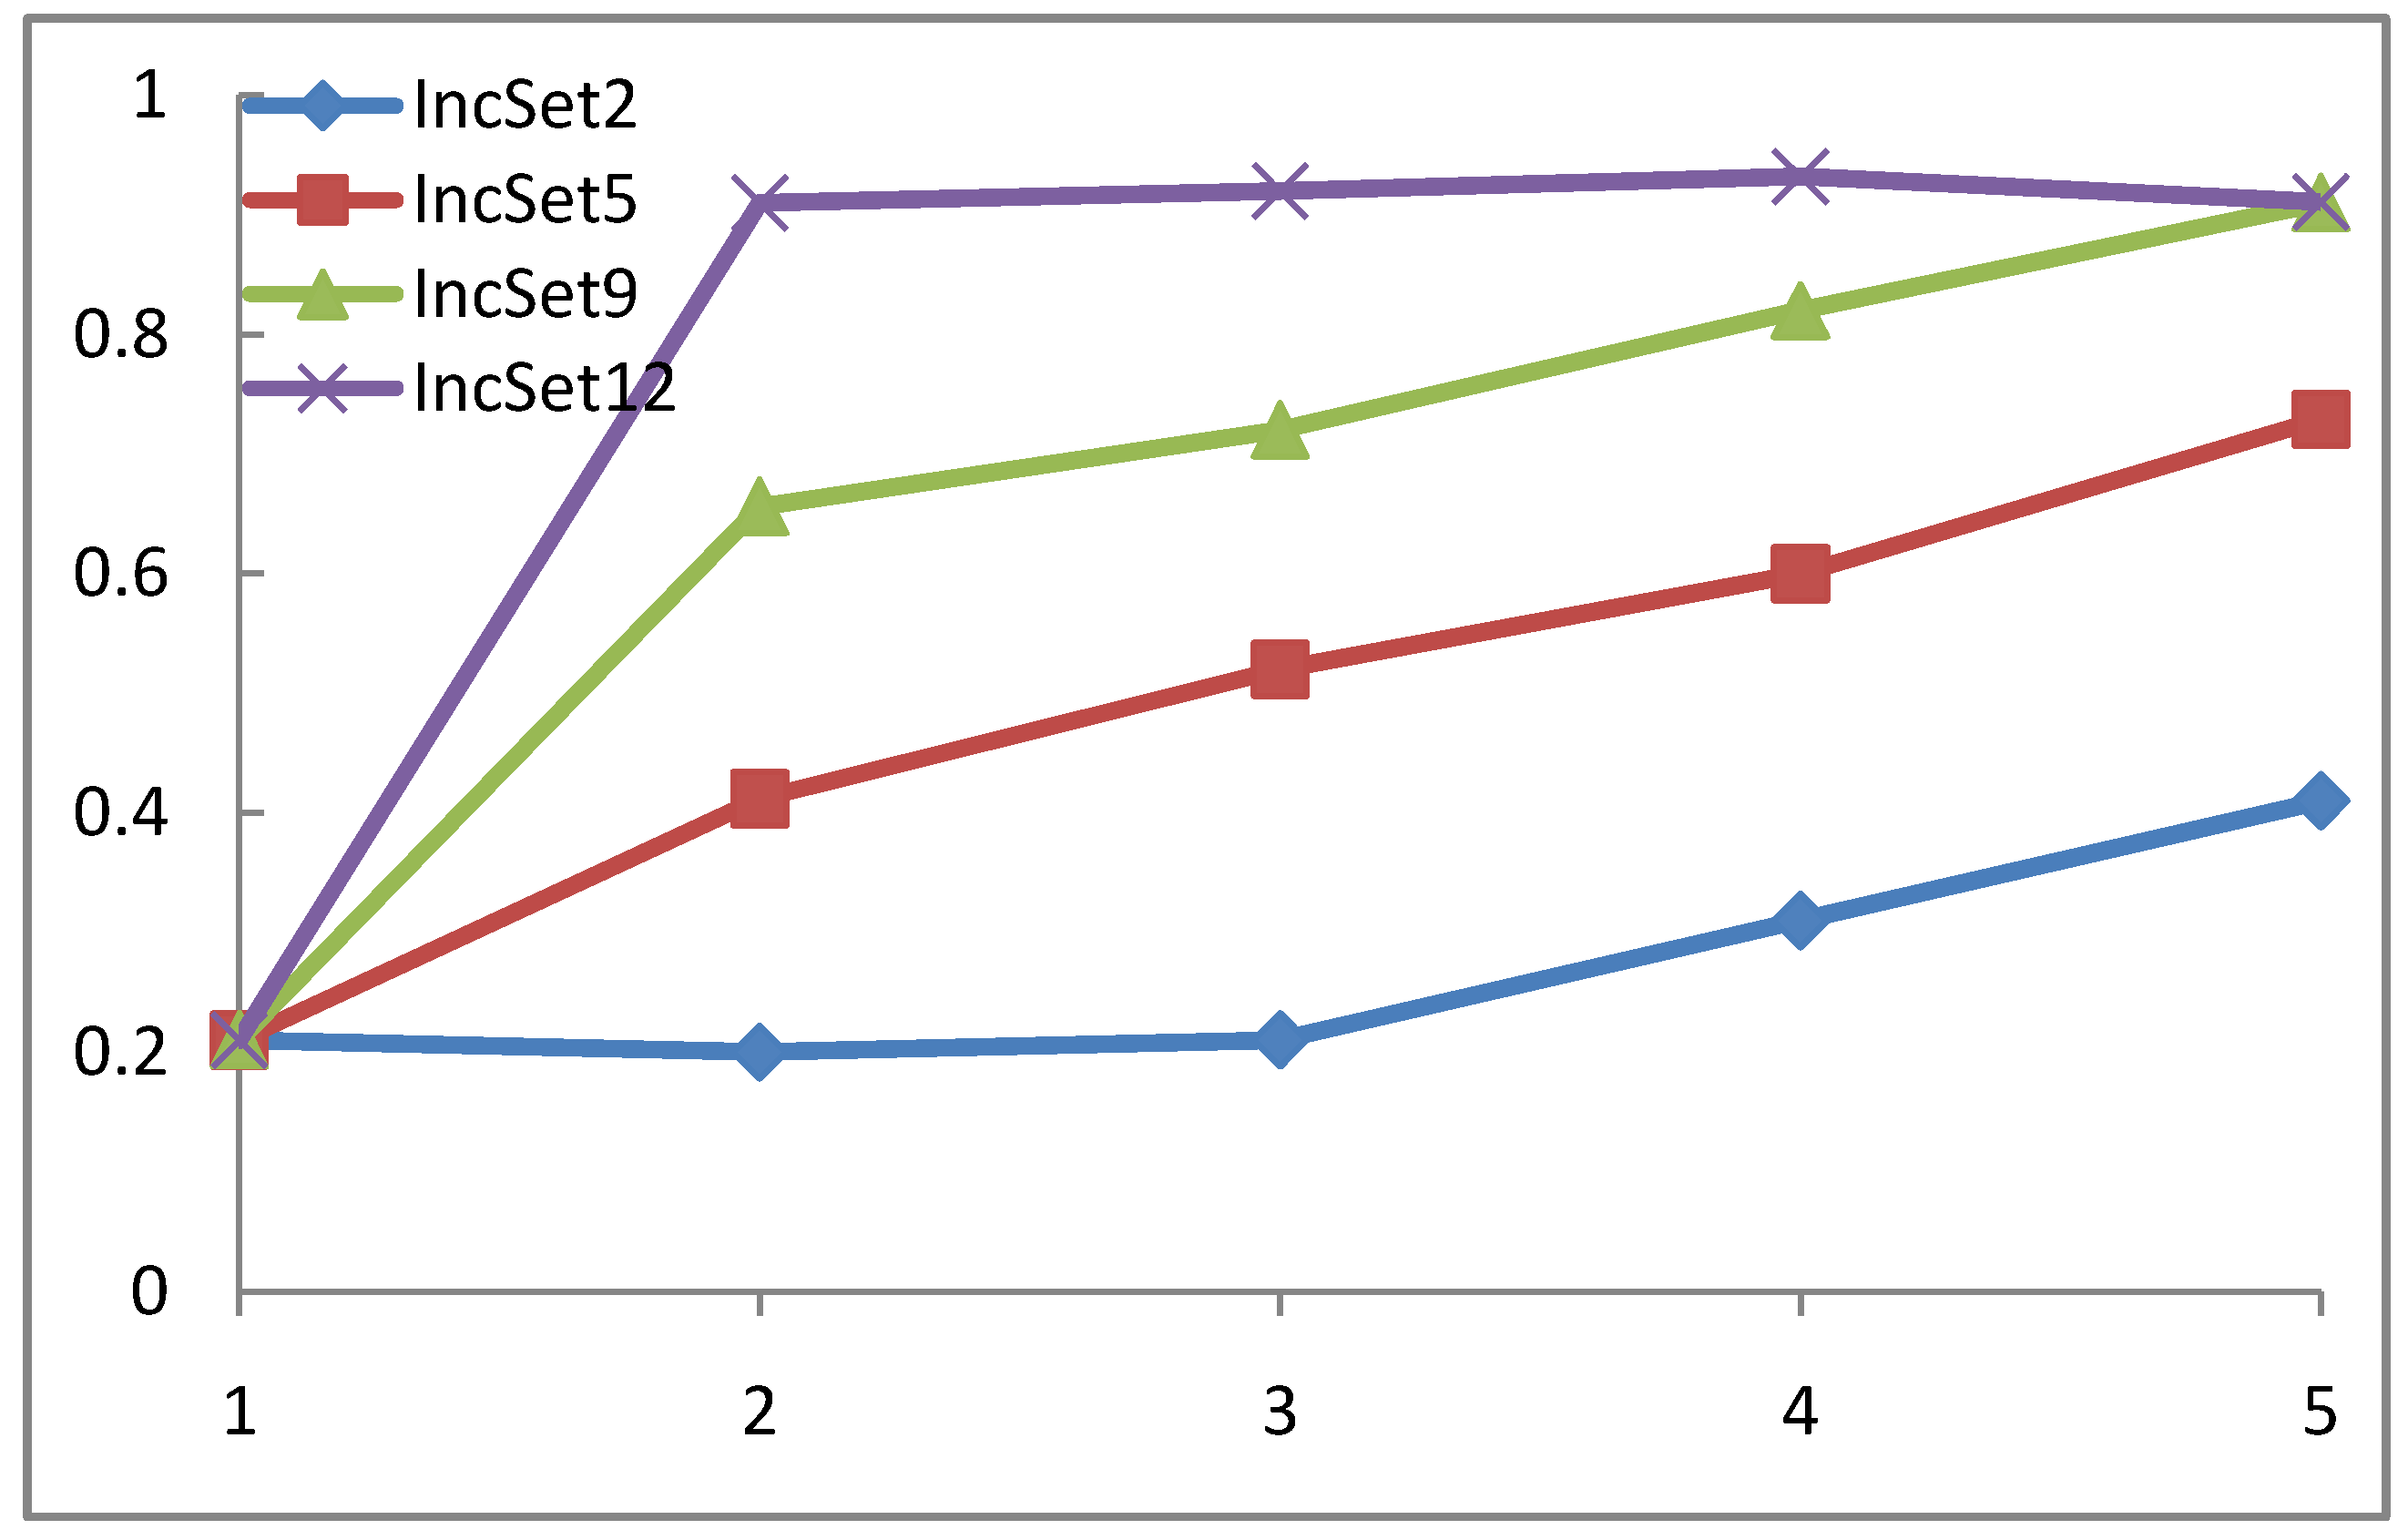

4.2. Performance and validation criteria for WP-SVM

4.4. WP-SVM Specificity and Storage Requirements

| Reference | Results | Settings |

| [33] | 95%, average of 1.5 false positive per patient | 72 patients, 144 data sets, 21 polyps >=5 mm in 14 patients |

| [34] | 90.5%, average of 2.4 false positive per patient | 121 patients, 242 data sets, 42 polyps >=5 mm in 28 patients |

| [35] | 80%, average of 8.2 false positive per patient | 18 patients, 15 polyps >= 5mm in 9 patients |

| [36] | 100%, average of 7 false positive per patient | 8 patients, 7 polyps>=10 mm in 4 patients |

| 50%, average of 7 false positive per patient | 8 patients, 11 polyps measuring between 5 – 9 mm in 3 patients | |

| [37] | 90%, average of 15.7 false positive per patient | 40 patients, 80 data sets,39 polyps>=3 mm in 20 patients |

| WP-SVM | 93.4% average of 3.2 false positive per patient | 169 patients, 28 polyps measuring between 6-9 mm and 33 polyps >10mm |